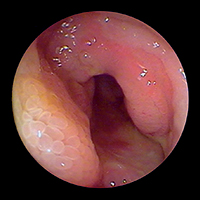

де еще «Push-and-Pull-Enteroskopie» (PPE). Уже из названия становится понятным и сам принцип этого предложенного в 2001 г. японцами (Yamamoto H. et al., 2001) и впервые в 2003 г. примененного на Западе исследования. Передвижение по тонкому кишечнику телескопически выдвигаемого зонда длиной около двух метров, состоящего из непосредственно энтероскопа и наружного зонда большего диаметра, осуществляется путем «нанизывания» на эндоскоп кишки, что становится возможным за счет периодического раздувания и перемещения относительно друг друга двух баллонов, один из которых находится непосредственно на конце эндоскопа, а другой — на конце наружного зонда. Так как по структуре своей двухбаллонный энтероскоп является обычным эндоскопом, он обладает и всеми его

преимуществами — возможностью промывать оптику во время исследования (что особенно ценно при диагностике кровотечений), проводить биопсии и, самое главное, осуществлять эндоскопические вмешательства. Именно поэтому зачастую капсульная эндоскопия (естественно, при положительном результате) дополняется двухбаллонной энтероскопией. Введение энтероскопа, как правило, осуществляется перорально ортоградно, только в редких случаях (например, при недостаточной инспекции кишечника или выявленной во время капсульной эндоскопии локализации источника кровотечения в дистальных отделах тонкого кишечника) необходимо дополнительное проведение ретроградной трансанальной энтероскопии. Длительность исследования составляет в среднем два часа, естественно, без внутривенного наркоза (как правило, хватает обычной седоанальгезии) тут не обойтись.

Первые результаты клинических исследований эффективности РРЕ выглядят весьма обнадеживающе — около 80% энтероскопий являются результативными. При этом в каждом втором случае было успешно проведено эндоскопическое лечение (лазерная коагуляция, дилатация стенозов или полип-

эктомия), а у каждого четвертого пациента это ис-

следование сыграло решающую роль в выборе дальнейшей медикаментозной тактики (как, например, при болезни Крона) или показаний к радикальному хирургическому лечению (при ее осложнениях).